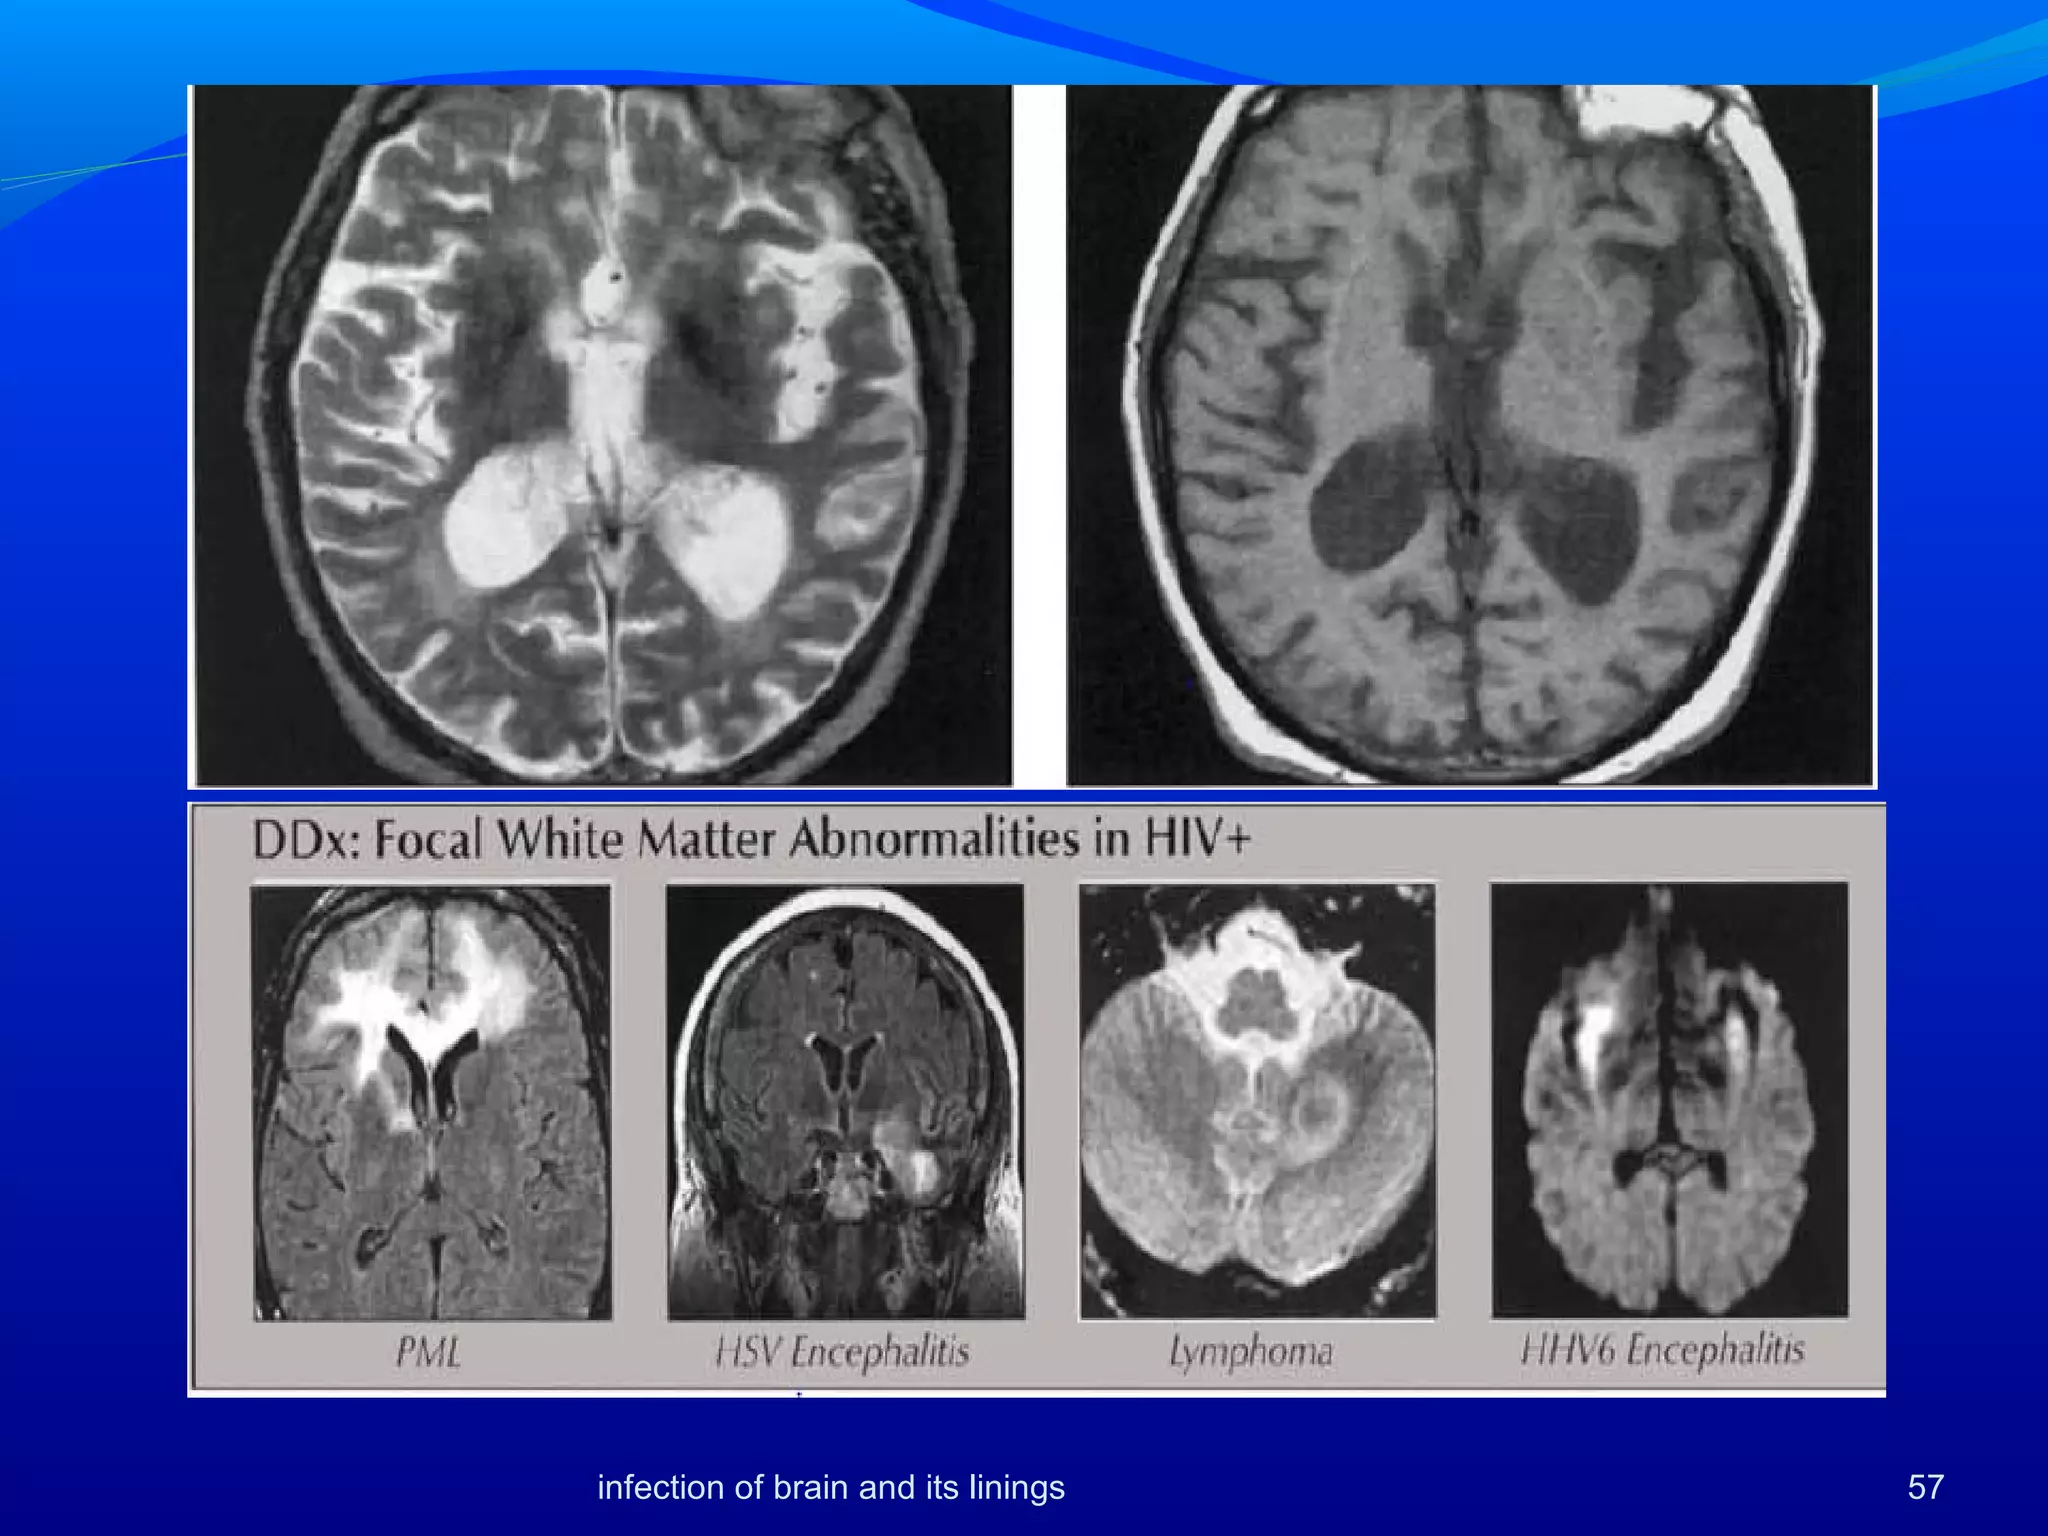

• 56.

HIV Encephalitis Syndrome ofcognitive, behavioral, and motor abnormalities attributed to direct HIV effect on brain, in the absence of opportunistic brain infections Location: Bilateral periventricular and centrum semiovale WM, basal ganglia, cerebellum, brainstem 56 Best diagnostic clue: Combination of atrophy and symmetric, periventricular or diffuse white matter (WM) disease suggests HIVE infection of brain and its linings

• 57.

57infection of brainand its linings